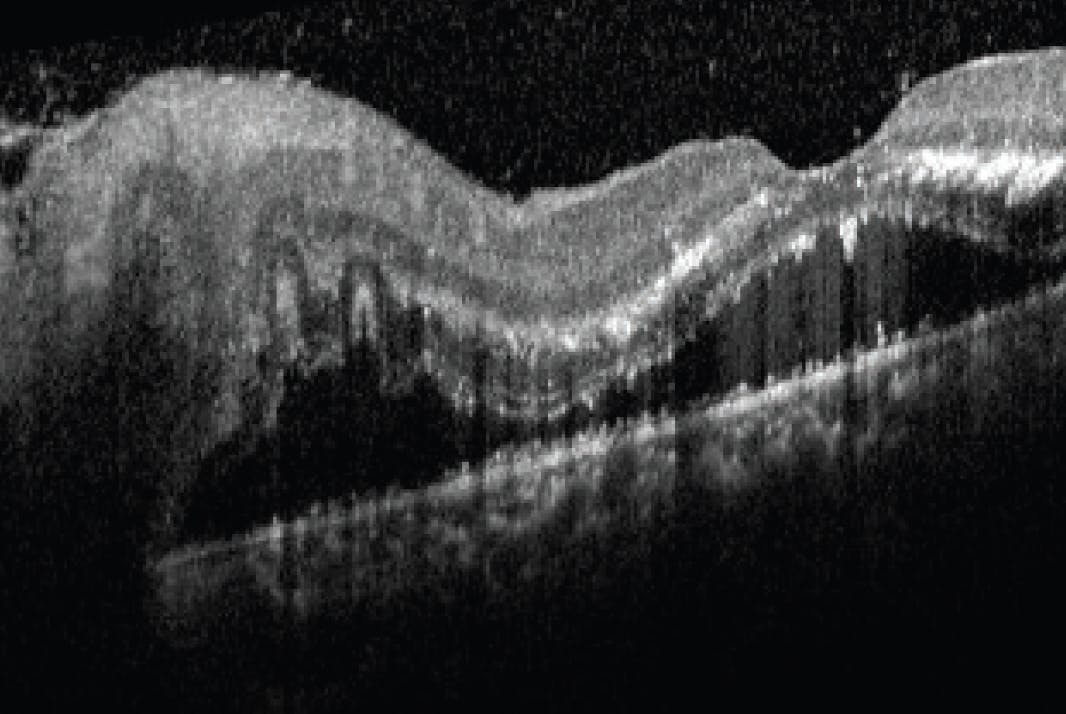

Posterior segment examination revealed disc edema that was greater in the left eye and macular edema with star pattern exudates OS and partial star pattern OD (Figure 1). OCT showed trace vitreous cell and subretinal fluid (Figure 2). Two multifocal white lesions of retinitis were noted OS nasally (Figure 3).

We discussed the likely diagnosis of CSD-NR given the clinical picture and history, and the decision was made to start oral doxycycline 100 mg twice daily for 4 weeks while awaiting serology results. At the 2-week follow-up visit, the patient’s vision had improved from 20/60 OD to 20/30 OD and from counting fingers OS to 20/60 OS with resolution of the relative afferent pupillary defect and subretinal fluid (Figure 4). He was seen again 2 weeks later after completing the course of doxycycline, at which point his nerve edema had resolved, although exudate deposits remained in the left fovea. His VA was 20/25 OD and 20/50 OS, likely due to remaining exudates. He was scheduled to return in 1 month but was lost to follow up.